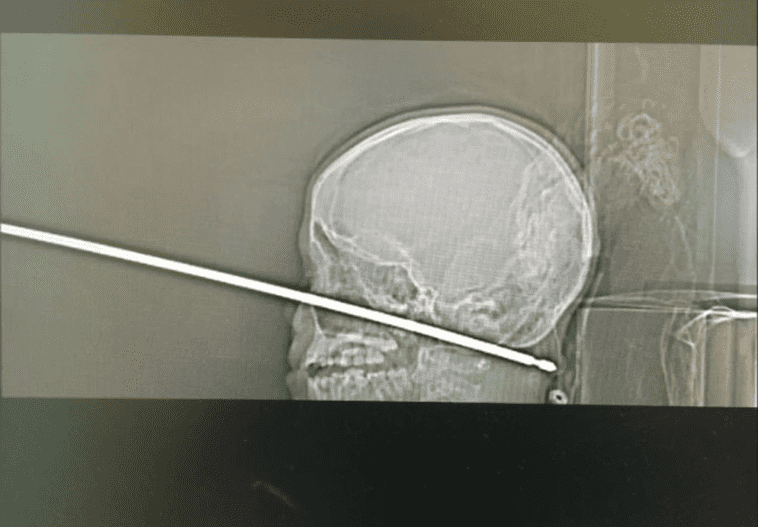

Car à ce moment-là, la vie du jeune Xavier était encore sérieusement compromise. Les scanners de son crâne ont montré que la broche a transpercé son visage et s’est logée jusque dans son cou, a déclaré le Dr Koji Ebersole, directeur de neurologie endovasculaire au système de santé de l'université du Kansas, où Xavier a été traité.

La broche est passée tout près de vaisseaux sanguins primordiaux, notamment l’artère carotide et l’artère vertébrale. "Si la broche s’était logée à un millimètre plus près, cela aurait probablement été une blessure insurmontable, a ajouté le spécialiste cité par le site Live Science. Selon les médecins, la broche à rôtir n’est pas non plus passée loin de son cerveau, du tronc cérébral et des principaux nerfs, ce qui aurait pu le laisser paraplégique ou hémiplégique. D’après le Dr Ebersole, Xavier avait "une chance sur un million" que la trajectoire de la broche n’atteigne aucun organe vital, aucun nerf ni aucune artère.